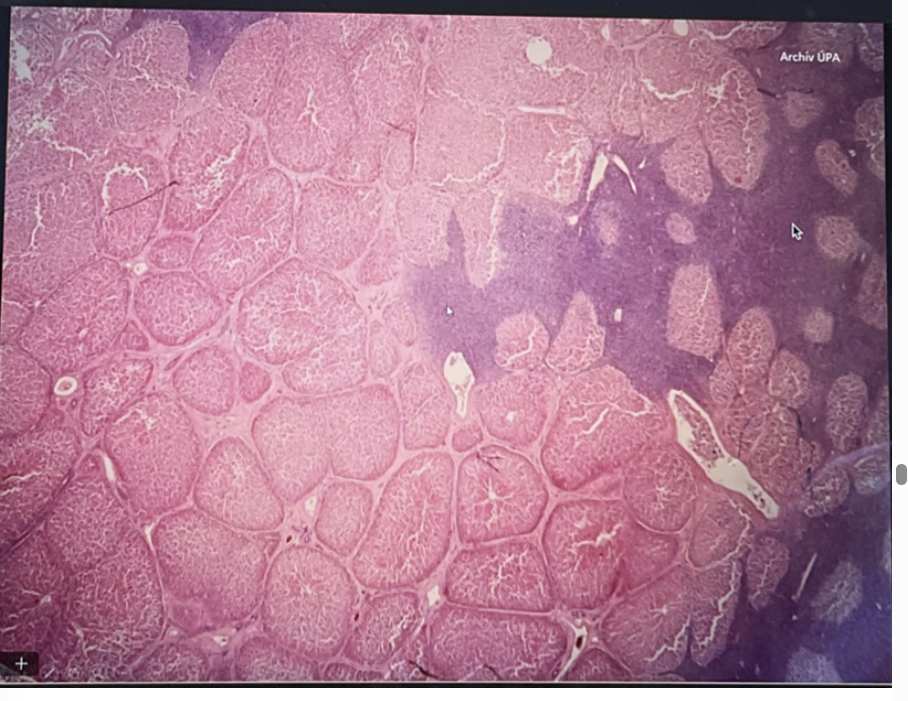

Leucosis lymphadenoidea hepatis - lymphosarcoma

one end of liver → basophilic stained tumor tissue formed by slightly differentiated lymphocytes